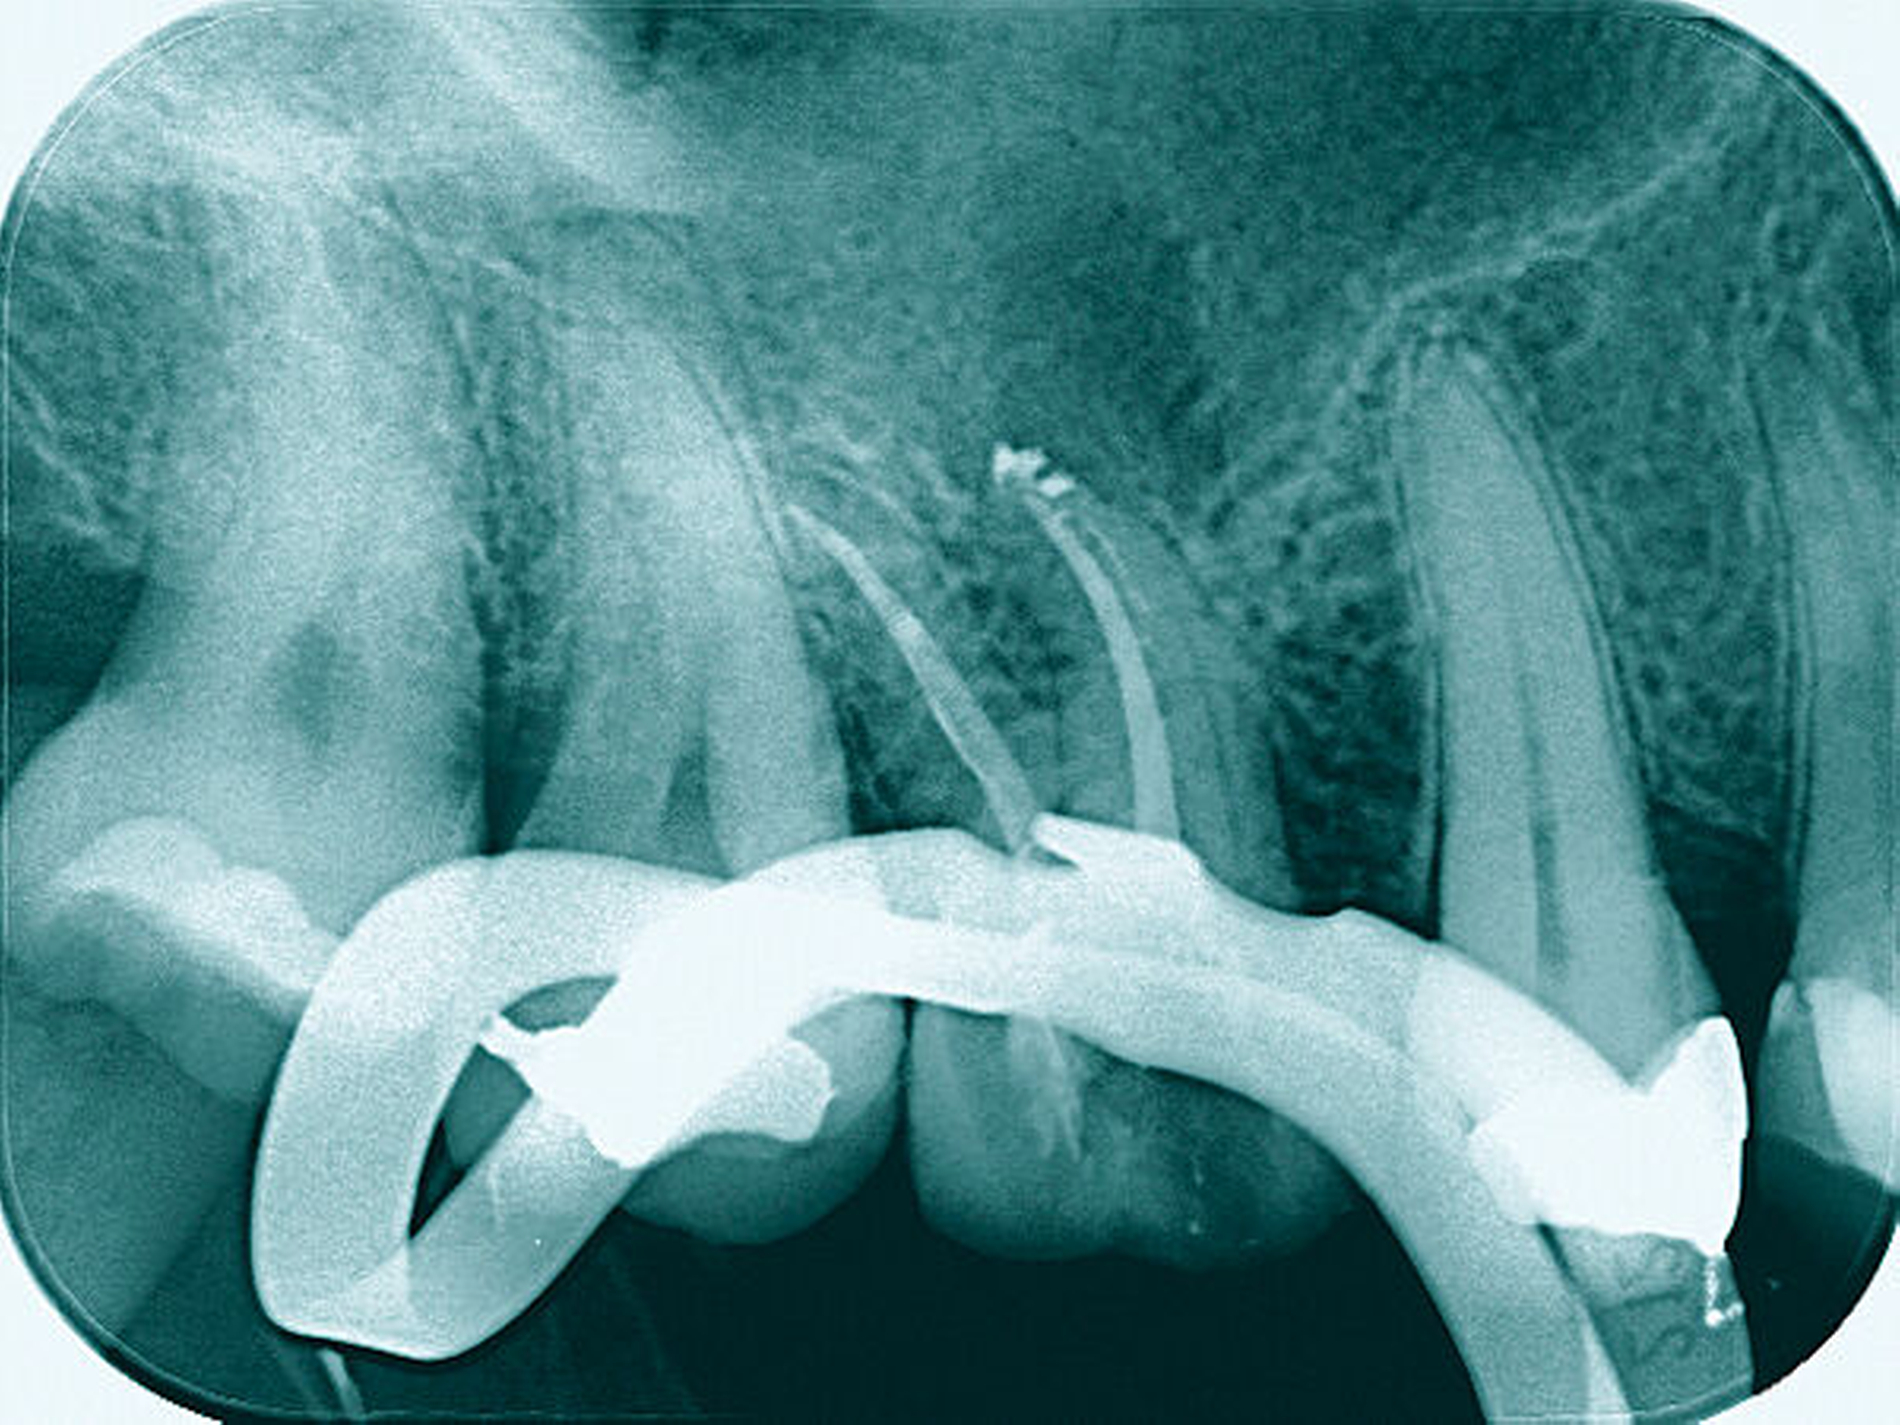

Nach der Anästhesie erfolgt bei einer beabsichtigten Entfernung einer der beiden bukkalen Wurzeln ein Ertasten der vestibulären Furkation. Wir halten es für ratsam, von der Furkation nach okklusal eine deutlich sichtbare Markierung mit einem wasserfesten Stift anzuzeichnen und diese Linie okklusal halbkreisförmig um die zu entfernende Wurzel zu verlängern. Das erleichtert die Orientierung beim Absetzen des zu entfernenden Zahnanteils. (Abbildung 1a).

Anschließend verwenden wir eine Lindemannfräse (H162SL, Firma Komet Dental, Lemgo) in einem Schnelllaufwinkelstück und trennen die Wurzel mitsamt des Kronenanteils vorsichtig entlang der zuvor angezeichneten Linie ab. Um den zu erhaltenden Zahnanteil nicht unbeabsichtigt mit der Fräse zu beschädigen, bleibt die Orientierungslinie zunächst unangetastet (Abbildung 1b).

Danach werden zunächst die dentogingivalen und die koronalen dentoalveolären Parodontalfasern der separierten Wurzel mit einem Periotom durchtrennt, anschließend wird die Wurzel mit Hebeln und Luxatoren gelockert. Falls erforderlich erfolgt die endgültige Entfernung mit einer Oberkiefer-Bajonettzange (Abbildung 1c).

Ein 59-jähriger Patient stellte sich erstmals 2015 mit rezidivierenden pochenden Beschwerden und zeitweise zusätzlich auftretendem Pusaustritt an Zahn 16 vor. Klinisch zeigte sich ein ausgeprägter Attachmentverlust distal mit bis apikal sondierbarer distobukkaler Wurzel, Furkationsbeteiligung und Pusaustritt sowohl über den Parodontalspalt als auch durch einen distobukkal gelegenen Fistelausgang. Zunächst erfolgte die endodontische Behandlung des Zahnes 16 mit anschließender systematischer PA-Therapie. Bei persistierender parodontaler Problematik an 16 wurde die Möglichkeit der Teilamputation der distobukkalen Wurzel mit dem Patienten diskutiert, um die Hygienefähigkeit und damit die Prognose des Zahnes zu verbessern. Auch über die Extraktion als Alternative wurde der Patient aufgeklärt. Er war allerdings motiviert, seinen Zahn so lange wie möglich zu erhalten.

Eine 53-jährige Patientin stellte sich 2015 mit plötzlich aufgetretenen, starken Beschwerden an Zahn 16 und der Bitte um Abklärung vor. Es erfolgte die klinische und röntgenologische Befundung des Zahnes, der neben einer apikalen Parodontitis auch eine große, fast bis in die Furkation reichende Kronenrandkaries an der mesiobukkalen Wurzel aufwies. Um diesen vorhersagbar versorgen zu können, wurde der Patientin die endodontische Behandlung mit Amputation der mesiobukkalen Wurzel und anschließender Versorgung mittels Vollkrone als Alternative zur Extraktion aufgezeigt. Sie entschied sich für den Zahnerhalt.

So folgte nach der Wurzelfüllung die Amputation der mesiobukkalen Wurzel. Der Zahn wurde nach der Amputation auf Wunsch der Patientin zunächst mit einem Langzeitprovisorium versorgt, das im Verlauf gegen eine definitive Versorgung ausgewechselt wurde. Die Patientin ist seitdem an 16 beschwerdefrei, der Zahn ist stabil und hat eine gute Langzeitprognose.